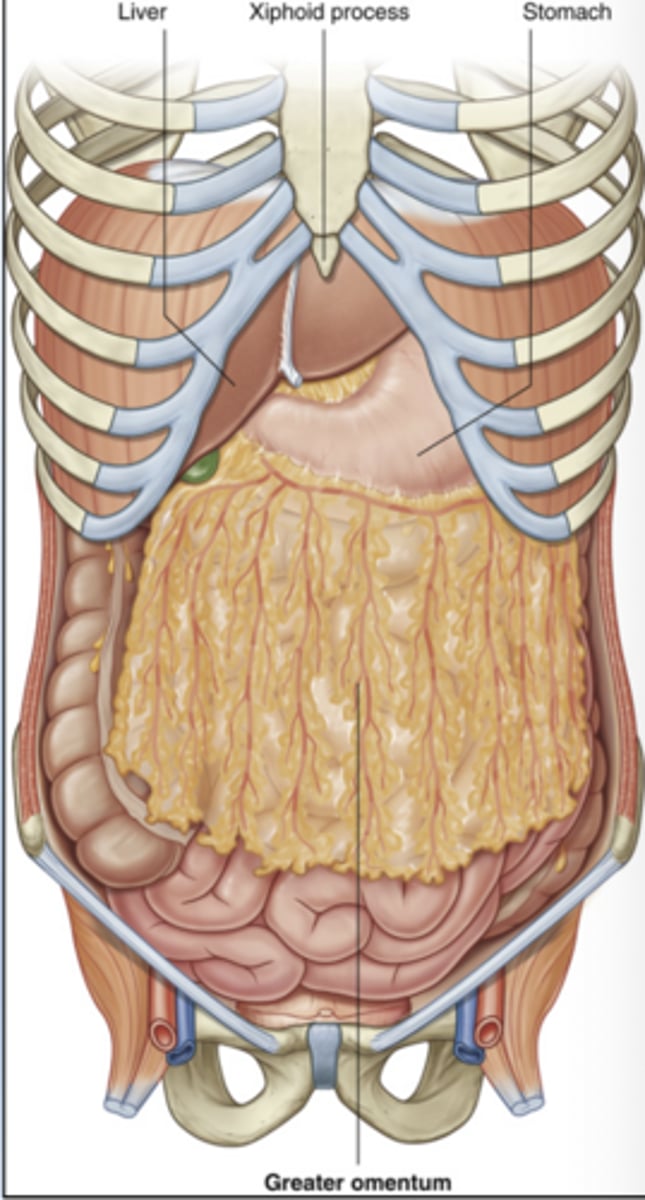

On anterior abdominal organ view, which organs are typically visible?

Liver occupies right upper quadrant, stomach lies left upper quadrant, transverse colon crosses abdomen, and small intestine occupies central abdomen.

What is the role of the greater omentum and why is it clinically important?

Protects abdominal organs, stores fat, and provides immune surveillance.

It can migrate toward inflamed areas.